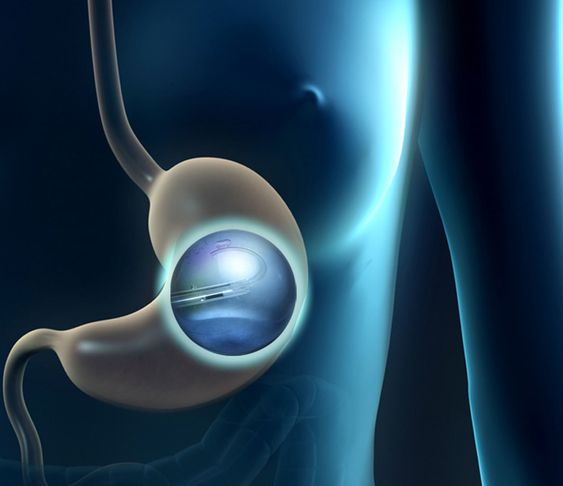

تعتبر عملية بالون المعدة واحدة من الخيارات الشائعة لفقدان الوزن، وتساعد الكثير من الأشخاص في الوصول إلى أهدافهم الصحية. ومع تزايد العيادات التي تقدم هذا النوع من الخدمات في الرياض، يصبح من المهم اختيار العيادة المناسبة. في هذه المقالة، سنقدم لك دليلً...

تعد عملية بالون المعدة واحدة من الخيارات الشائعة لفقدان الوزن للأشخاص الذين يعانون من السمنة أو زيادة الوزن. إنها تتضمن وضع بالون مملوء بالغاز أو السائل داخل المعدة، مما يساعد على الشعور بالشبع وتقليل كمية الطعام المتناولة. في هذه المقالة، سنستعرض ال...

تعد مشكلة الوزن الزائد من أكثر التحديات الصحية انتشارًا في الوقت الحالي، ويبحث الكثيرون عن حلول فعالة وآمنة لإنقاص الوزن. يعتبر بالون المعدة في الرياض أحد الخيارات البارزة التي توفر حلاً غير جراحي لفقدان الوزن. لكن هل هذا الإجراء مناسب للجميع؟ في هذا...